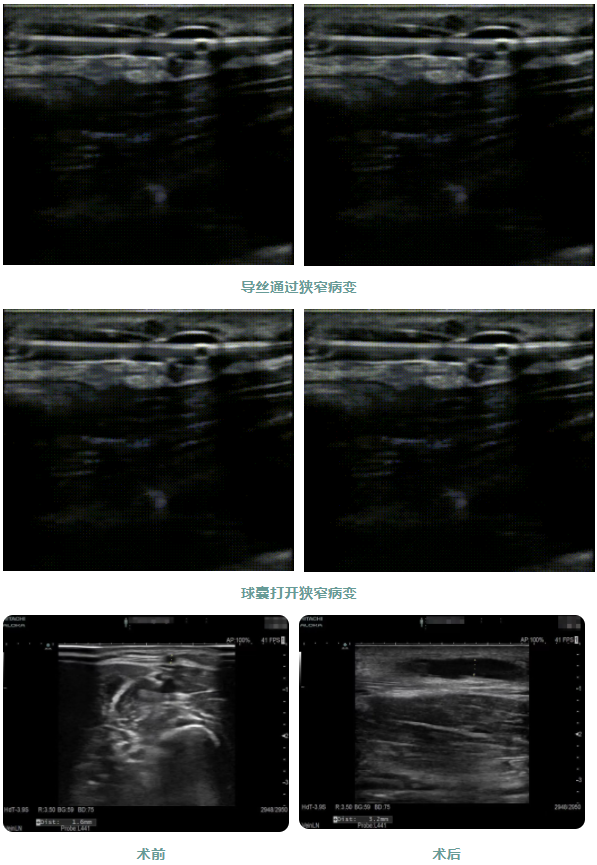

患者1年前出現(xiàn)周身乏力伴有雙下肢水腫癥狀,在外院行“為腎透析的動靜脈造瘺術(shù)”后規(guī)律透析治療。因內(nèi)瘺無震顫2日,為求系統(tǒng)治療來院,入院后腎內(nèi)科金明花主任帶領(lǐng)醫(yī)護團隊立即完善相關(guān)檢查,診斷為:動靜脈內(nèi)瘺血栓形成,經(jīng)超聲檢查發(fā)現(xiàn)動靜脈內(nèi)瘺血栓形成狹窄,最窄處內(nèi)徑約1.6mm。

為了節(jié)約患者有限的血管資源,盡早治療,經(jīng)過腎病內(nèi)科金明花主任及科室共同討論并爭得患者家屬同意后,決定對患者進行超聲引導(dǎo)下動靜脈內(nèi)瘺球囊擴張術(shù)+血栓碎栓術(shù)解決內(nèi)瘺狹窄及血栓。手術(shù)過程中金明花主任在內(nèi)瘺狹窄位置近心端進行穿刺,沿穿刺針置入導(dǎo)絲、置入血管鞘,在超聲實時引導(dǎo)下球囊到達病變部位,緩慢擴張球囊,解決狹窄病變,并壓碎血栓,使內(nèi)瘺通暢。整個手術(shù)僅用30分鐘,用時少,效果明顯,術(shù)后內(nèi)瘺血管雜音及震顫明顯,手術(shù)效果立竿見影。